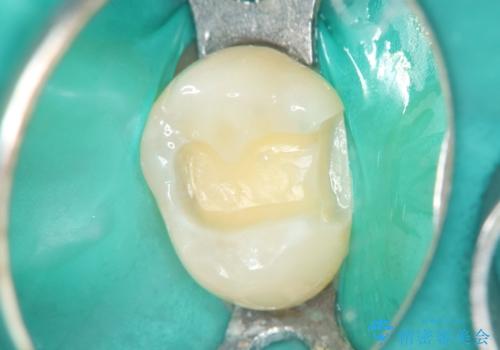

今回の治療では、虫歯の大きさや深さに応じて、異なるセラミック修復法を適用しました。

比較的軽度な虫歯には、セラミックインレー(詰め物)で対応し、健全な歯質を最大限に残しました。

進行した虫歯や歯の強度が低下している歯には、セラミッククラウン(被せ物)を選択し、歯全体を保護することで破折を防ぎました。

短期間での治療を可能にしつつ、天然歯と見分けがつかない審美性と、長期的に安定する機能性を兼ね備えたセラミック修復を実現しました。